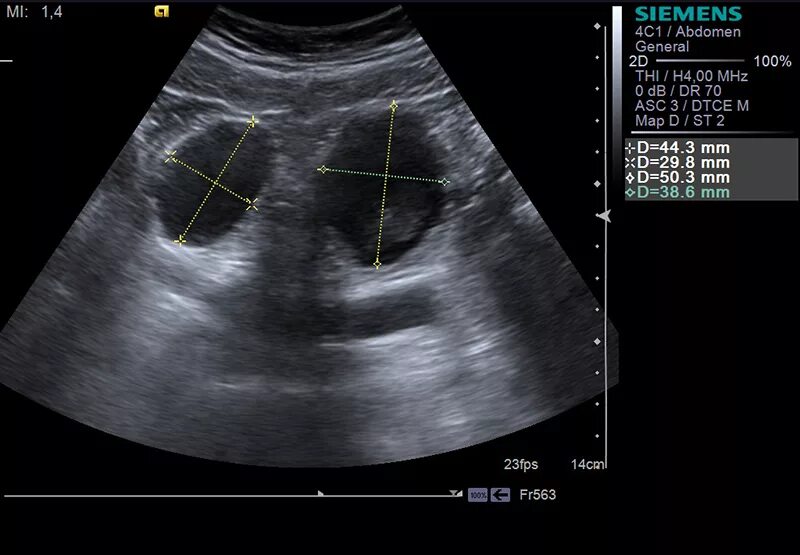

Трансабдоминальное узи